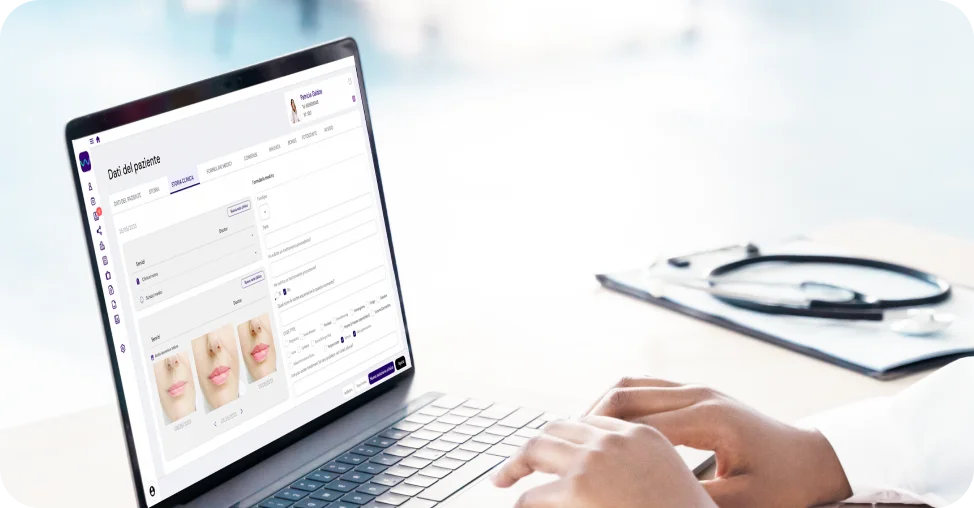

Gestisci facilmente tutti i processi della tua clinica, affidandoti a strumenti digitali sviluppati dal punto di vista del medico, come una cartella clinica completa, fotografie e annotazioni, tracciabilità delle scorte, firma digitale e marketing di follow-up.

Archivia in modo sicuro la documentazione medica del paziente e monitora la tracciabilità dei materiali di consumo per preservare la sicurezza del paziente.